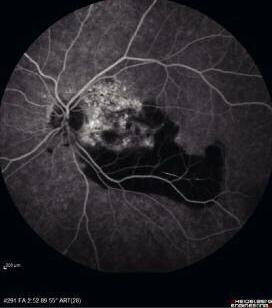

18 giorni dall’esplosione, il segmento anteriore dell’OS si presentava in quiete con una emorragia sottocongiuntivale in riassorbimento Per quanto osservabile, il cristallino e le altre strutture non apparivano alterate All’esame del fondo oculare si evidenziava una vasta emorragia sottoretinica a verosimile partenza coroideale che coinvolgeva il polo posteriore e la regione maculare In sede subfoveale la tomografia a coerenza ottica (OCT) e la fluorangiografia (FAG) mostravano una lesione ipereflettente sottoretinica a margini definiti ed iperfluorescente nei tempi precoci e tardivi senza segni di leakage (Figg. 1 e 2).

During fundus examination, a wide subretinal haemorrhage, apparently starting from choroid, appeared and involved the posterior pole and macular region in left eye. Optic Coherence Tomography (OCT) and Fluorescent Angiography (FAG) showed a subretinal hyperreflective lesion with defined border that was early and late hyperfluorescens with no signs of leakage (Figures 1, 2)